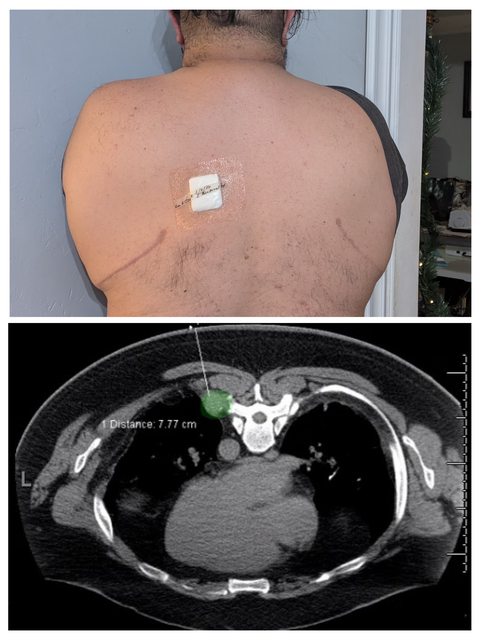

I went in to have my first round of palliative chemo today to find that my freshly installed medical port isn't working. It looks kinked on today's x-ray, compared to last Thursday.

I went in to have my first round of palliative chemo today to find that my freshly installed medical port isn't working. It looks kinked on today's x-ray, compared to last Thursday.

In November of 25 a new spot was found growing in my left lung by CT. In December another in the soft pleural wall tissue, found via PET scan. Early January determined it wasn't surgically viable.